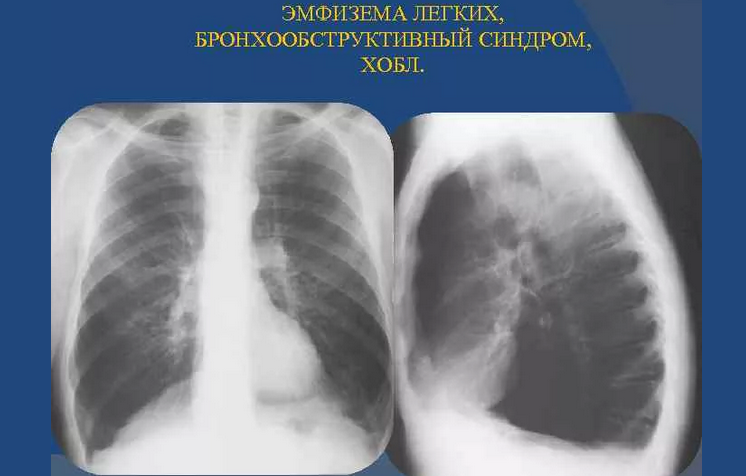

Рентгеновские снимки при врожденной эмфиземе легкого

Раздел: Визуальные уроки